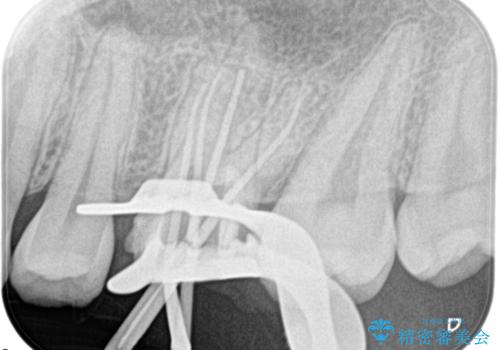

大きい虫歯 根管治療〜オールセラミッククラウン

- 歯が欠けたことを主訴に来院されました。

再根管治療後、歯周外科を行い、オールセラミッククラウンにて修復処置を行っております。

根管治療を行った大臼歯は速やかに被せ物の治療を行うことが必要です。